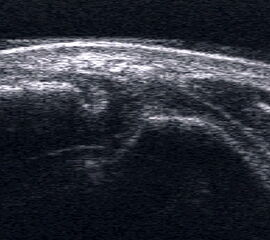

Bursitis subachillea

Bursitis subachillea als echoarme Struktur an der kranialen Kante des Kalkaneus.

Abbildung 66

Lagerung: Bauchlage, ggf. Sprunggelenk mittels Rolle unterstützt.

Schnittführung: LS und TS über dem Achillessehnenansatz.

Referenzstruktur: Kalkaneus.

Befunde: Im dorsalen LS findet sich im Winkel zwischen Achillessehne und Calcaneus eine meist echofreie lokale Raumforderung, ggf. mit dorsaler Schallauslöschung (Abb. 66).